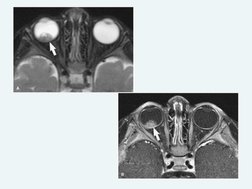

• Imaging: Retinoblastoma: Features MRI and ultrasound images depicting retinoblastoma in different stages and types for diagnostic evaluation.

Macam Retinoblastoma

Endophytic retinoblastoma

It grows inwards from the retina into the vitreous cavity.

Calcification (+)

Exophytic retinoblastoma

It grows outwards and separates the retina

from the choroid.

Opacity associated with retinal detachment.

Calcification (+).